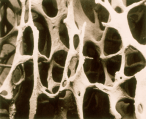

- Osteoporosis and metabolic bone diseases

• Osteoporosis